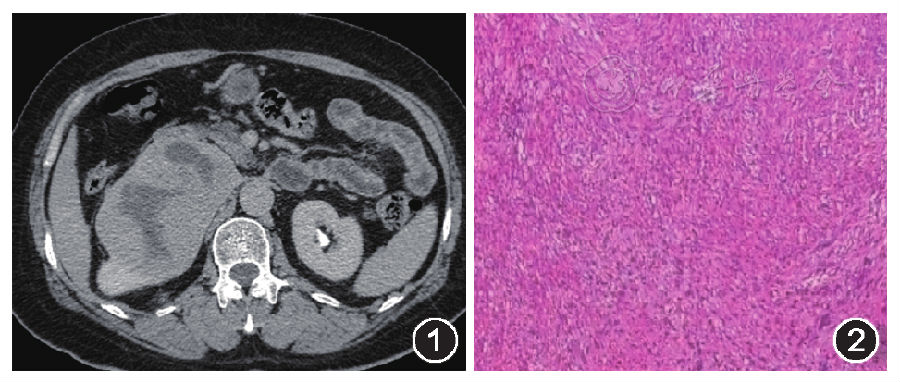

示右肾上极卵圆形囊实性肿块,未见钙化,病灶边界清晰,边缘规整,最大横断面大小约100 mm×75 mm,肿块实性部分CT值约37HU;增强扫描(动脉期)示病灶实性部分轻度强化,延迟扫描病灶实性部分进一步持续强化(图1),三期扫描均低于肾实质强化程度,囊性部分未见强化。右侧肾盂受压,肾盏轻度扩张,右侧肾筋膜未见明显异常,肾血管显影良好,腹主动脉周围及后腹膜未见肿大淋巴结影。CT诊断:右肾占位,恶性可能性大。

图1肾神经鞘瘤CT增强扫描图

图2肿瘤组织低倍镜下病理(HE染色,×40)示瘤细胞呈梭形,局部细胞丰富

:肿瘤境界清楚,由纤维包膜包绕,镜下见肿瘤细胞呈梭形,呈束分布,少数区域有栅栏状结构(图2),低倍镜下由典型的antoni A区和antoni B区构成。免疫组化染色检测:CD34(-),CD99(+),CKpan(-),DM(-),HMB-45 (-),Ki-67 (+5%),P53(+),NSE(+),S-100(+),SMA(-),Vimentin(+),EMA(-)。病理诊断:肾神经鞘瘤。